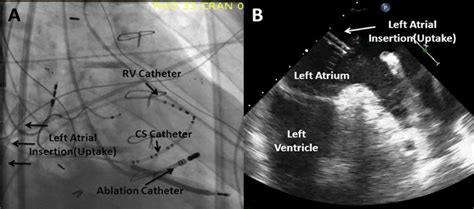

Coronary Sinus Anatomy Fluoroscopy : Fluoroscopy showing three diagnostic electrophysiology ... - It returns the majority of the blood supply for the left ventricle to the right atrium.

Ventricular Arrhythmias Arising From the Left Ventricular ...

Ventricular Arrhythmias Arising From the Left Ventricular ... from www.ahajournals.org

Fluoroscopy in the RAO view shows recording and ablation ...

Fluoroscopy in the RAO view shows recording and ablation ... from www.researchgate.net